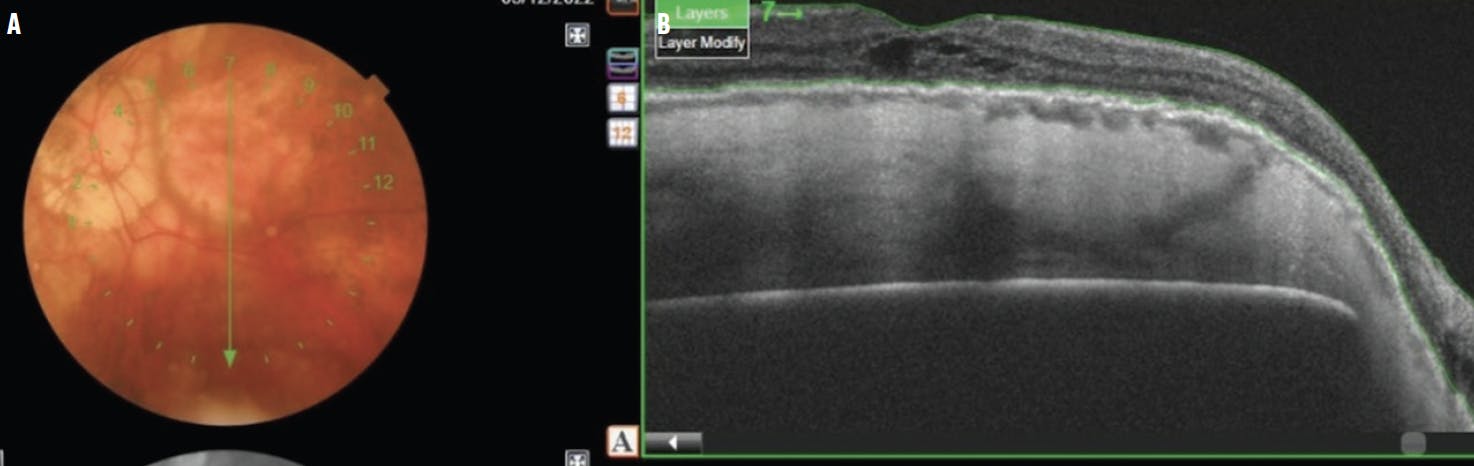

We placed this implant in a highly myopic eye that presented with a retinal detachment and maculoschisis (Video). At presentation, the patient was phakic with a moderate degree of cataract and a VA of hand motion in the right eye. The axial length of the eye was 28.77 mm, and the patient refracted to -11.25, -2.00 axis 72. Widefield imaging and OCT showed a staphyloma, a retinal detachment, and myopic maculoschisis (Figure 2).

<p>Figure 2. The preoperative color photo of the posterior pole (A) and OCT scan (B) showed a staphyloma and myopic maculoschisis. Note the retinal detachment in the fovea.</p>

Figure 2. The preoperative color photo of the posterior pole (A) and OCT scan (B) showed a staphyloma and myopic maculoschisis. Note the retinal detachment in the fovea.